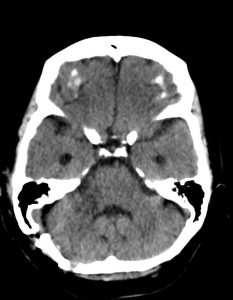

Ασθενής γυναίκα 68 ετών με προοδευτική επιδείνωση της ακοής δεξιά και επεισόδια ιλίγγων και διαταραχής της ισορροπίας και βάδισης.

Η μαγνητική τομογραφία εγκεφάλου ανέδειξε χωροκατακτητική εξεργασία στη δεξιά γεφυροπαρεγκεφαλιδική γωνία συμβατή με ακουστικό νευρίνωμα (αιθουσαίο σβάννωμα) και πίεση επί του στελέχους (Koos IV).

Η ασθενής υπεβλήθη σε δεξιά οπισθοσιγμοειδική κρανιοτομία και ολική αφαίρεση της βλάβης.